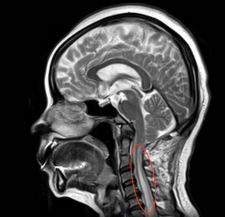

刘女士一家觉得颈椎手术风险太大,保险起见,刘女士慕名找到betway在线登陆周围神经修复外科,希望靠手外科医生丰富的门诊经验帮她解决这一难题。手外科陈步国主任不单纯考虑是肘管综合征,随后便让刘女士拍了头颈部核磁,这才发现刘女士竟患有“脊髓空洞症”。随后陈主任对刘女士这一情况启动了多学科会诊,结合影像资料,终于找到真凶,原来这的确不是单纯的肘管综合征,也不是所谓的颈椎病,而是颅底凹陷症。

术前,郭宗扬教授和神经外科董伟主任带领团队制定了周密的手术计划,决定为患者施行“开颅后颅窝减压术”。术中在郭宗扬教授的指导下,神经外科董伟主任娴熟的避开椎动脉,保护好脊髓,使用超声铣刀将寰椎后弓切除、枕骨大孔扩大,后颅窝充分减压,患者的“生命通道”被重新打开,受压的脊髓重新膨起,出血仅100毫升,所有的医护终于松了一口气。

专家提醒,如果出现行走不稳、肢体麻木无力等症状,不仅要考虑常见的腕\肘管综合征、颈椎病、腰椎间突出症等,也要当心颅底凹陷症。据郭教授介绍,齿状突向后向上的病人要前入路(从口腔),而这个病人是寰枕融合畸形,是从延髓的后方向前压迫而造成的症状。若患者颈部疼痛、四肢乏力、麻木、四肢或者双下肢感觉分离即疼温觉减退,触觉存在,应考虑合并脊髓空洞症。尽管它的发病率不高,但会引起严重的后果。要早发现、早诊断、早治疗,不要病急乱投医以延误病情。